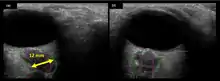

The astronauts affected by long term visual changes and prolonged intracranial hypertension have all been male, and SOS may explain this because in men, the sternocleidomastoid muscle is typically thicker than in women and may contribute to more compression. The reason that SOS does not occur in all individuals may be related to anatomic variations in the internal jugular vein. Ultrasound study has shown that in some individuals, the internal jugular vein is located in a more lateral position to Zone I compression, and therefore not as much compression will occur, allowing continued blood flow.

Intracranial pressure (ICP) needs to be directly measured before and after long duration flights to determine if microgravity causes the increased ICP. On the ground, lumbar puncture is the standard method of measuring cerebral spinal fluid pressure and ICP,[6][44] but this carries additional risk in-flight.[4] NASA is determining how to correlate ground-based MRI with inflight ultrasound[4] and other methods of measuring ICP in space is currently being investigated.[44]